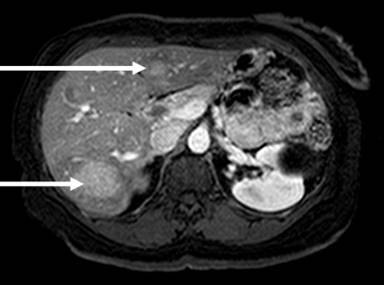

Neuroendocrine tumors (NETs) of the gastroenteropancreatic tract are a rare and heterogeneous form of cancer that span variable tissue subtypes with behavior patterns that reflect their invasive potential. The biological behavior of these cancers is reflected in the pathological grade ascribed to these lesions at the time of biopsy. Grading schema for these lesions help characterize a less aggressive subtype (i.e., carcinoid of the gut) from more aggressive subtypes that behave with great similarity to small cell lung carcinomas. The use of mitotic rate and Ki-67 forms the basis for assigning grade, with lesions having high levels of mitoses and Ki-67 reflecting a more aggressive pattern of biological behavior. Well differentiated NETs may have a protracted progression and cause very little symptoms, behaving as indolent neoplasms even in the metastatic setting. Poorly differentiated lesions can present with a variety of symptoms and the potential for wide metastatic spread and organ compromise (Figures 1 and 2).

Figure 1. MRI of a patient with pancreatic neuroendocrine tumor spread to the liver (arrows). |